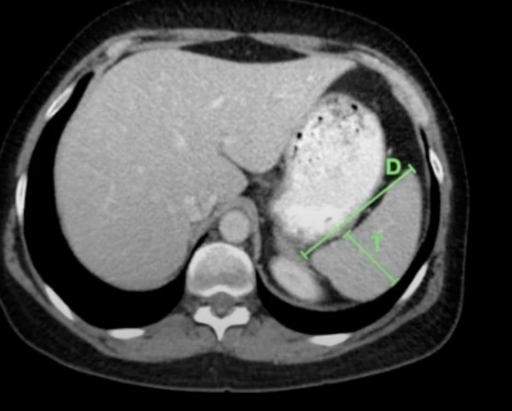

Qué se ve en la TC de bazo?

A

• Densidad intermedia (hígado)

• Forma semilunar

Estudio para ver el Bazo más accesible para dx de esplenomegalia

USG

- Volumen